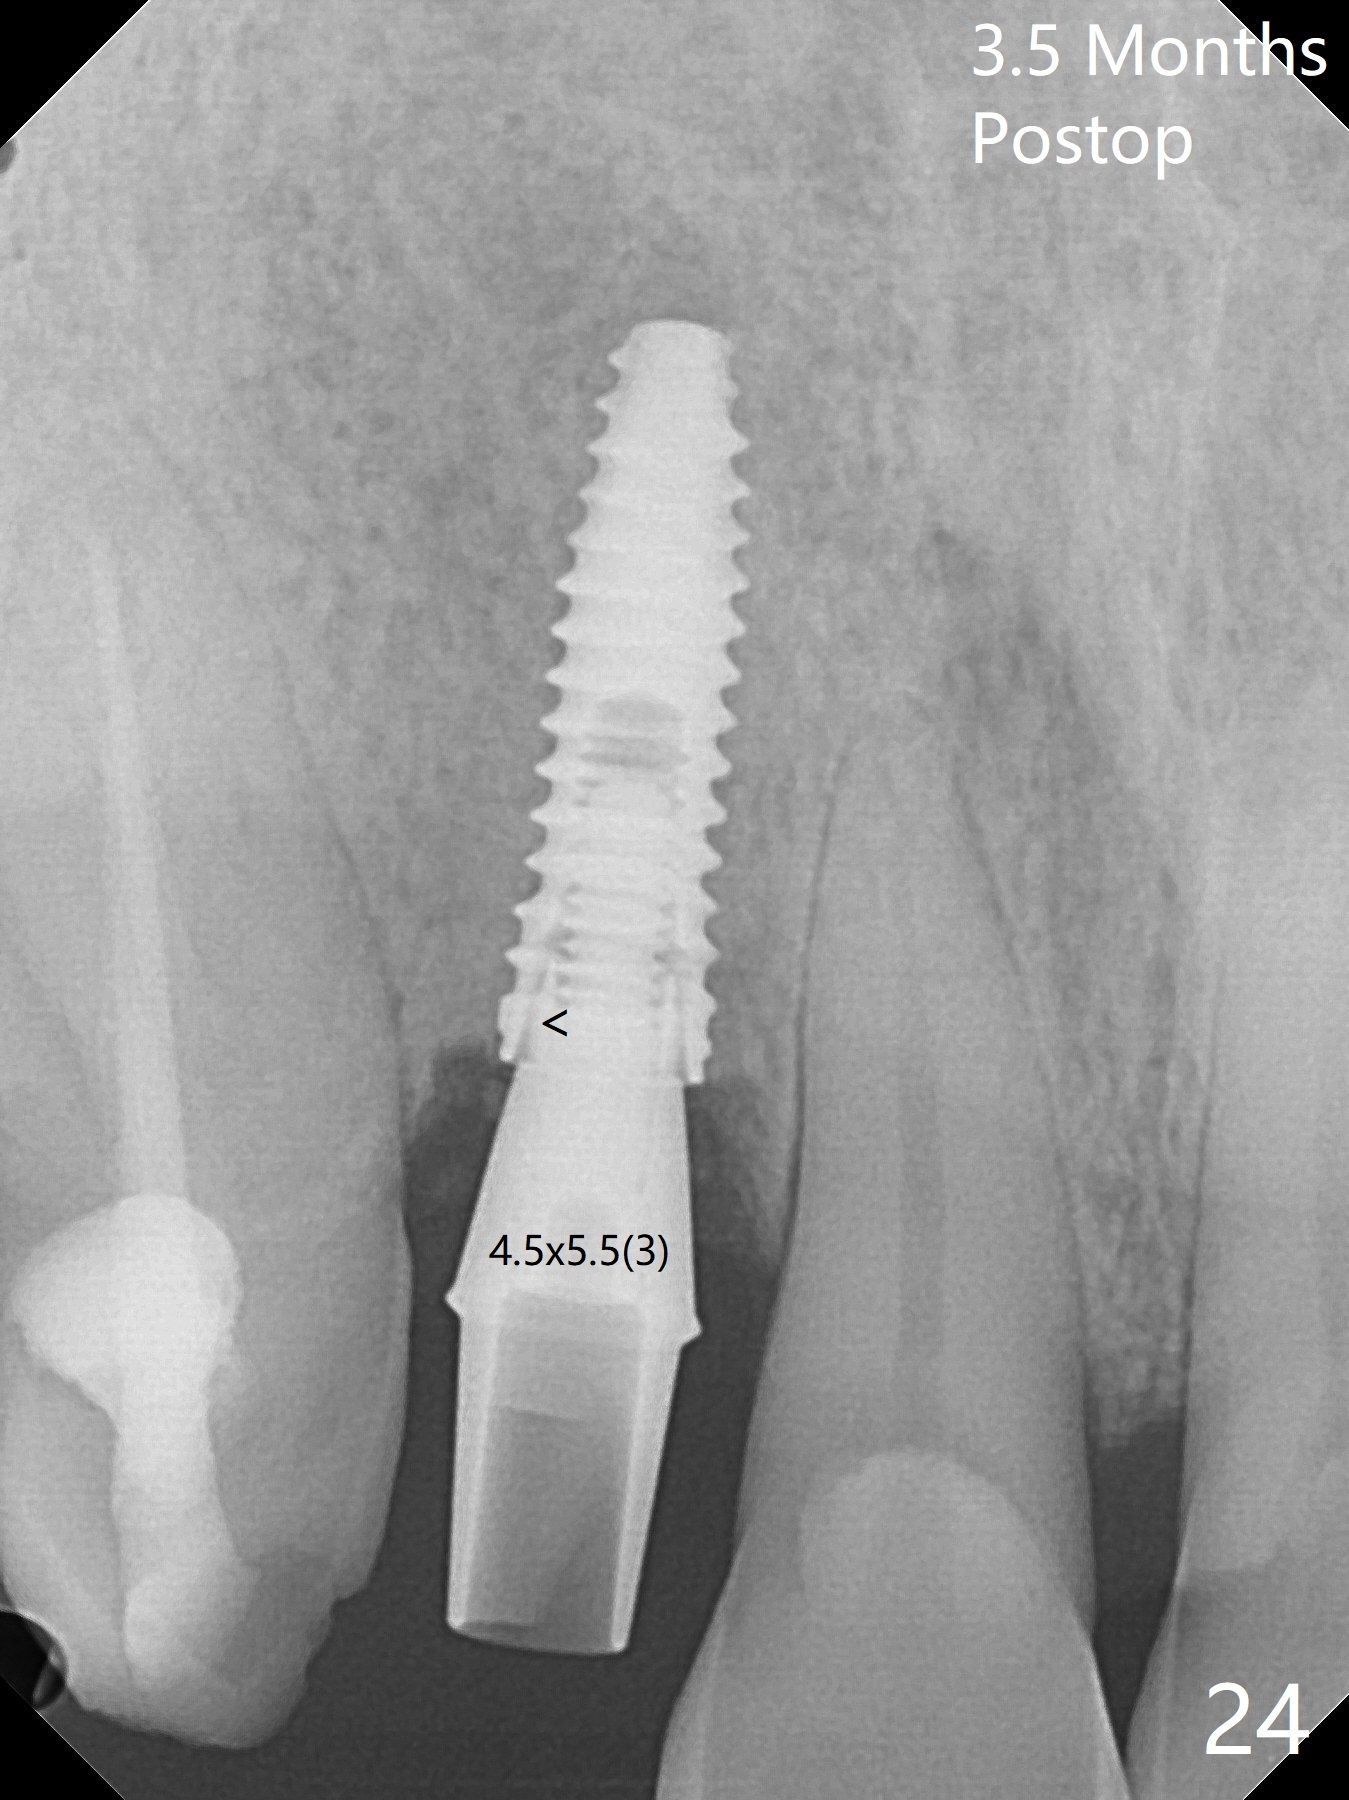

An apical abscess is present when the patient returns for immediate implant at #7 (Fig.1 *); a 2nd challenge is deep bite. After smooth extraction, the apical buccal plate is found to be perforated. Following debridement, a piece of gauze is placed in the apical defect for hemostasis, while osteotomy is initiated palatal (Fig.2). The apical defect seems to be extensive (Fig.3 yellow dashed line). A new trajectory is intended (red arrow) without much success. Before implant placement, bone graft is placed in the apical defect defect area, while a drill (Fig.4 D) is inserted in the finished osteotomy (Fig.5 O). In spite of seemingly large apical defect, the buccal crest bone exists (Fig.4 x). A 3x14(2) mm 1-piece implant is placed with stability; the first round of bone graft is apparently around the apical portion of the implant (Fig.6 *). The coronal end of the implant has to be adjusted several times buccopalatally to accommodate the deep bite. A 2nd round of bone graft following an immediate provisional closes the coronal space of the socket (Fig.7 *). CT will be taken to show the bone graft to repair the buccal plate defect when the patient returns for postop follow-up. In fact the defect is minimal in CT a month ago. The fistula does not disappear 1 week postop, but it is non tender (Fig.8). The patient complains of asymptomatic swelling in the right nostril. CT shows that the large buccal perforation is repaired with large amount of bone graft (Fig.9,10 *). It would be nicer to place the implant slightly more buccal apically (Fig.11 red lines; Fig.12 (preop design)). The buccoapical fistula disappears nearly 1 month postop (Fig.13). The apparently "lifeless" bone graft seems to be harmonious with the surrounding tissue (Fig.14). The periimplant gap reopens with implant mobility nearly 4 months postop (Fig.15), which is related to micro-movement associated with the immediate provisional. The latter is removed. A larger 2-piece implant will be placed in a 2-staged manner if needed (Fig.16). In fact the 3x14 mm straight 1-piece implant (Fig.17) has no mobility when it is retightened, but the trajectory remains buccal. Incision shows that there is no implant thread exposure. A 3x14 mm 15 degree angled 1-piece dummy implant is able to establish the correct trajectory, but there is no occlusal clearance (Fig.18). Micromovement during osteointegration may recreate loosening. Finally using Lindamann bur, the osteotomy is changed so that a 3.5x13 mm 2-piece implant does not need an angled abutment to establish occlusion (Fig.19). There is one palatal thread exposure. Allograft is placed circumferentially, followed by Human Amnion-Chorion Allograft and Collagen Plug. The wound does not heal 8 days postop (Fig.20), as related to the age (79 years old)? The wound appears to heal with a membrane on the surface (Amnion-Chorion one?) 3 weeks postop (Fig.21). The ridge looks wide 3.5 months postop (Fig.22,23). A 4.5x5.5(3) mm appears to be seated incompletely with a gap between the abutment and the implant (Fig.24<). A provisional is fabricated after heavy palatal reduction. Two months later, the provisional fractures. After repositioning the abutment with complete seating and torque (Fig.25), impression is taken. Although the buccal plate is concave, the gingiva remains healthy 10 months post cementation (Fig.26,27).